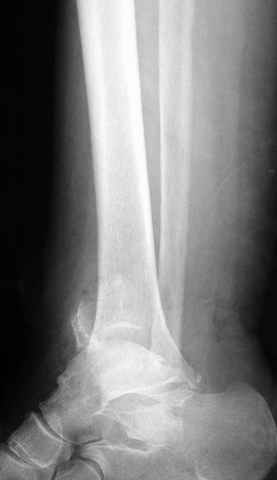

Pilon fracture:

ET> ЕЧ При подобных переломах фиксация малоберцовой кости обеспечивает

ET> низведение латерального тибиального фрагмента - появляется ориентир для

-Появляется ориентир и остов, на чем можно строить восстановление, почему сперва малоберцовую, впервые обьяснили и описали (Pylon type and Ankle fractures) в середине 50х Rienau и Gay.

Восстановливая длину и ротацию малоберцовой кости, затем относительно легче произвести реставрацию остальных элементов перелома дистального эпиметафиза болшеберцовой кости.

где исследования на трупах показали, что малоберцовая кость участвует в стабильности голеностопного сустава, поддерживая наклон тарана (talar tilt) за счет связок. После ознакомления работой Ramsey в ортопедию ввели термин "при переломах голеностопного сустава смещенная

таранная кость следует за малоберцовой костью" т.е. связка не рвется, а тянет таран за собой, поэтому восстановление малоберцовой кости в

первую очередь, затем остальных элементов - стал классическим при лечении данной патолгии. Латеральная колонна (столб), дистальный

конец малоберцевой кости, к нему прикрепляется латеральный суставной фрагмент дистального эпиметафиза большеберцовой кости (как на снимке)

и таранная кость, которые при репозиции малоберцовой кости репонируются автоматически.